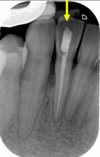

list the steps in what you can see on a radiograph as periapical inflammatory pathology develops

68